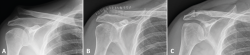

The two patients in which initial correct reduction of the joint was not achieved were seen to group most of the complications. The first patient, a 52-year-old woman with type IV acromioclavicular dislocation operated upon after four weeks of pain and dysfunction refractory to conservative management, presented insufficient reduction (54% displacement), progressive loss of reduction (finally 132%) and a poor functional outcome 14 months after surgery (Constant-Murley = 54; Quick-DASH = 69; ASES-shoulder = 57) - with evident scapular dyskinesia and clear anteroposterior and craniocaudal instability of the distal clavicle (Figure 3). The patient declined any other additional procedures. The second patient, a 50-year-old man with type V acromioclavicular dislocation subjected to conservative management during four months without success, presented initially insufficient reduction (43%) with progressive loss of reduction (74% at the end of follow-up), osteolysis of the distal clavicle and widening of the proximal orifice of the clavicle to 7.7 mm. These findings nevertheless had no functional repercussions, since after 18 months of follow-up the functional outcome was very good (Constant-Murley = 94; Quick-DASH = 88; ASES-shoulder = 99).

Figure 3. A 52-year-old woman with type IV acromioclavicular dislocation (A) subjected to surgery four weeks after injury due to refractory pain and dysfunction. The surgical outcome was considered acceptable, though with insufficient reduction (B). Fourteen months after surgery, the patient suffered persistent symptoms and loss of reduction was seen to have progressed (C).